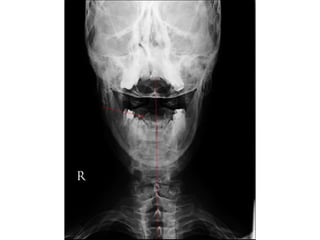

Radiological Assessment

• Cervical –X- Ray

Lateral

A-P especially (( Odontoid # type 2 ))

Open mouth

• CT thin cuts with reconstruction ( sagittal, Coronal )

Odontoid #

Anderson and D Alonzo classification 1974

Radiological Assessment • Cervical–X- Ray Lateral A-P especially (( Odontoid # type 2 )) Open mouth • CT thin cuts with reconstruction ( sagittal, Coronal ) • MRI